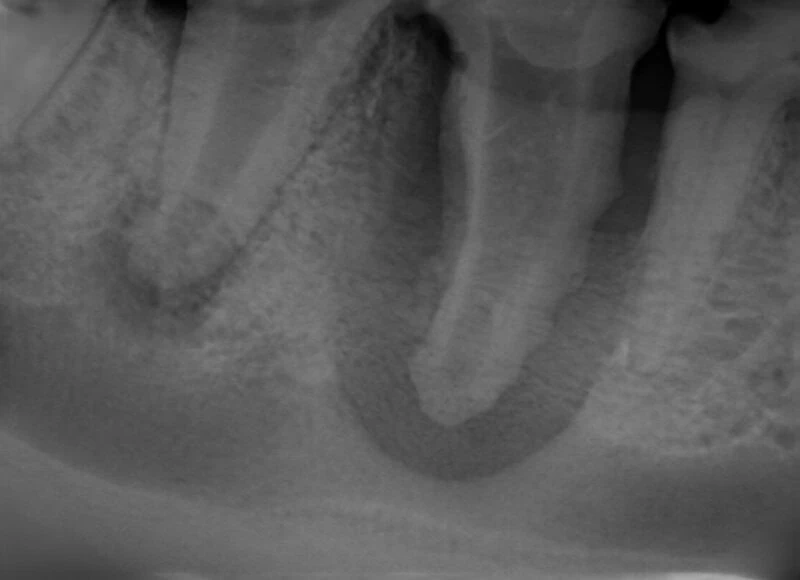

A relaxed and interactive online learning session focused on improving confidence in interpreting dental radiographs in small animal practice.

Each session will review real clinical cases, discussing radiographic findings, common pitfalls, and practical tips for everyday dentistry. We will also include discussion of evidence-based treatment options and clinical decision making.